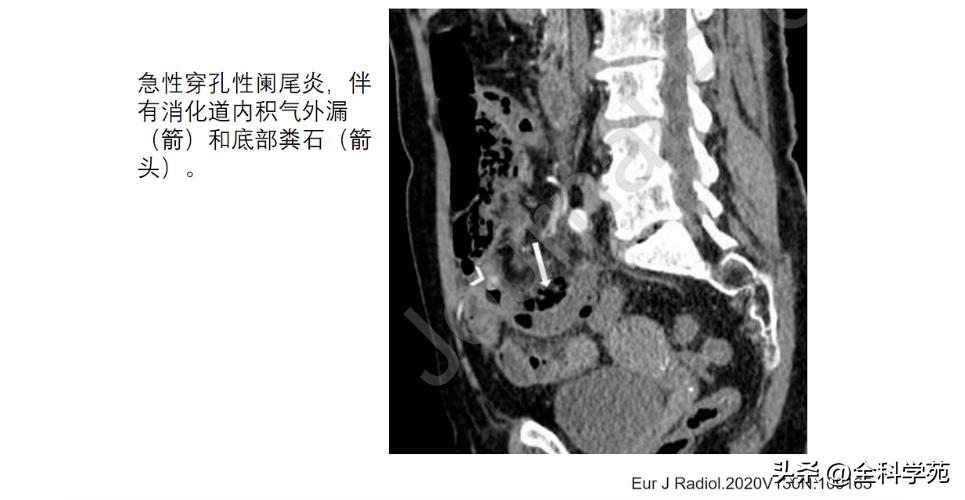

◆ 穿孔 (Perforation)

◆ 局部低强化是穿孔征象

◆ 蜂窝织炎和脓肿 (Phlegmon and abscess